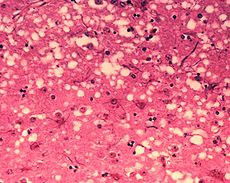

Prions cause neurodegenerative disease by aggregating extracellularly within the central nervous system to form plaques known as amyloid, which disrupt the normal tissue structure. This disruption is characterized by "holes" in the tissue with resultant spongy architecture due to the vacuole formation in the neurons. Other histological changes include astrogliosis and the absence of an inflammatory reaction. While the incubation period for prion diseases is generally quite long, once symptoms appear the disease progresses rapidly, leading to brain damage and death. Neurodegenerative symptoms can include convulsions, dementia, ataxia (balance and coordination dysfunction), and behavioural or personality changes.